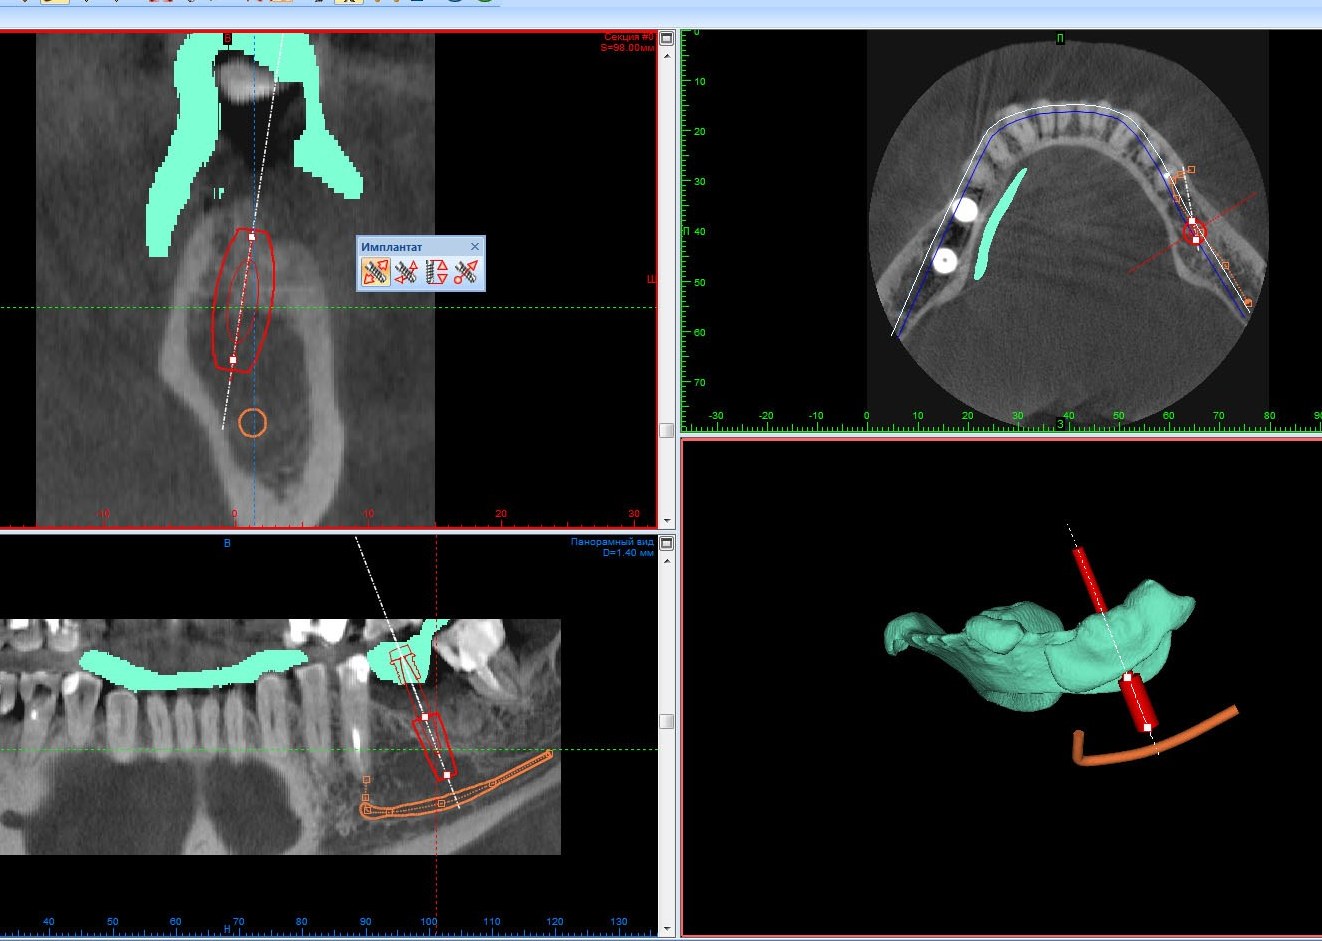

Для правильного позиционирования зубных имплантатов в кости мы применяем хирургические шаблоны, а также специальное програмное обеспечение с необходимыми "виртуальными" имплантатами, в которую мы загружаем данные компьютерной томограммы. Таким образом, каждая операция дентальной имплантации предварительно отрепетирована нами.

В некоторых случаях установку имплантатов необходимо производить с дополнительной костной пластикой, как на картинке.